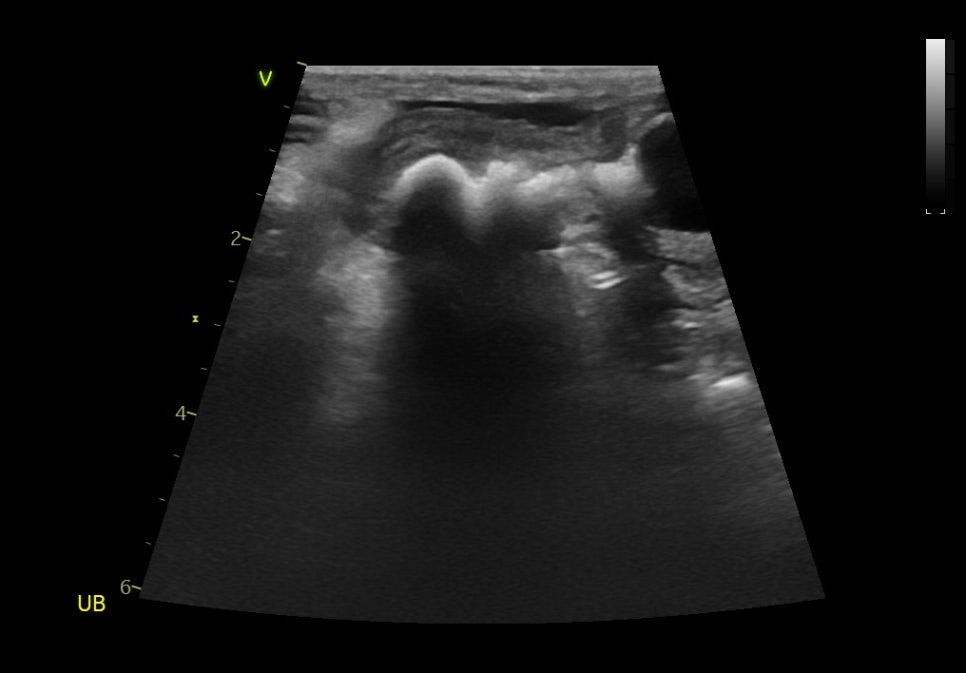

내원 당시 초음파 검사 결과 / 출처: 24시온숲동물의료센터

응급 진료 후 방사선(X-ray)과 초음파 검사 결과, 요도를 막고 있는 큰 결석이 확인되었으며, 이 결석이 요도를 막고 있어 소변 배출이 불가능한 상태였습니다.